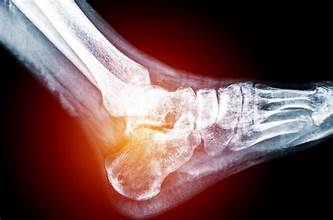

الاقتصادي- يمكن أن يصاب الشخص بضعف العظام في أي مرحلة عمرية إذ لا يرتبط دائمًا بالتقدم في السن، وبحسب ما نشرته صحيفة Times of India، فإن بعض الشباب اليوم يعانون بصمت من انخفاض كثافة العظام بسبب أنماط الحياة الخاملة والوجبات الغذائية الفقيرة بالعناصر الغذائية والاعتماد المتزايد على الوجبات السريعة. ينصح الأطباء بتناول مكملات الكالسيوم وفيتامين D، ولكن هناك أيضًا أطعمة فعّالة ومجربة، يمكن أن تُحسّن صحة العظام بشكل ملحوظ خلال 30 يومًا فقط، كما يلي: